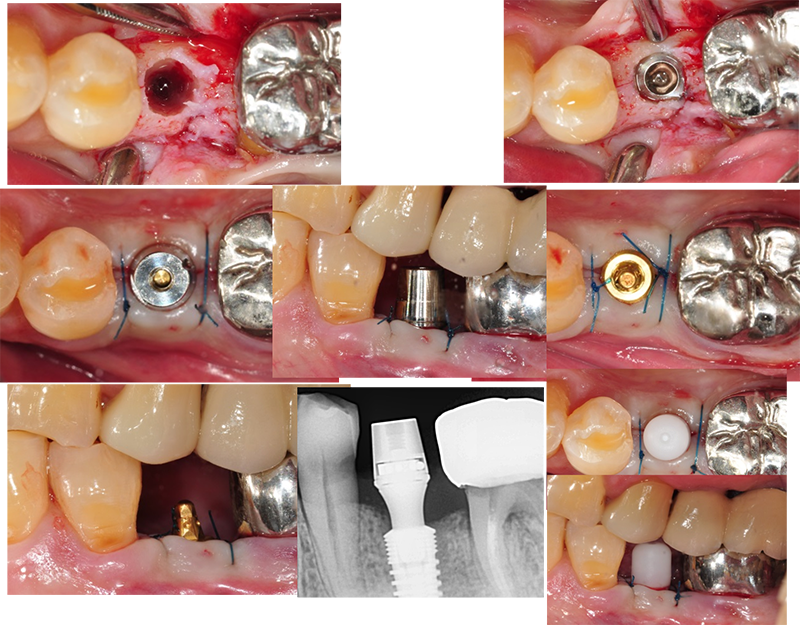

바로 Ezc의 convertible abutment(Ezc ab)를 장착할 수 있다. 매우 안정적인 보철 디자인이 될 수 있다.

수술하고 바로 convertible abutment인 Ezc ab를

장착하고 인상을 채득했다. 임시보철물을 만들기 위해서다.

Ezc convertible

abutment를 위치시킬 때 수술 직후이므로 잇몸보다 1.0~1.5mm 하방에 위치시키면 좋겠다.

Abutment level

impression(fixture level impression이 아니고) 즉 지대주 레벨 인상이다. 물론 보철도 지대주 레벨의 보철 디자인이 될

것이다.